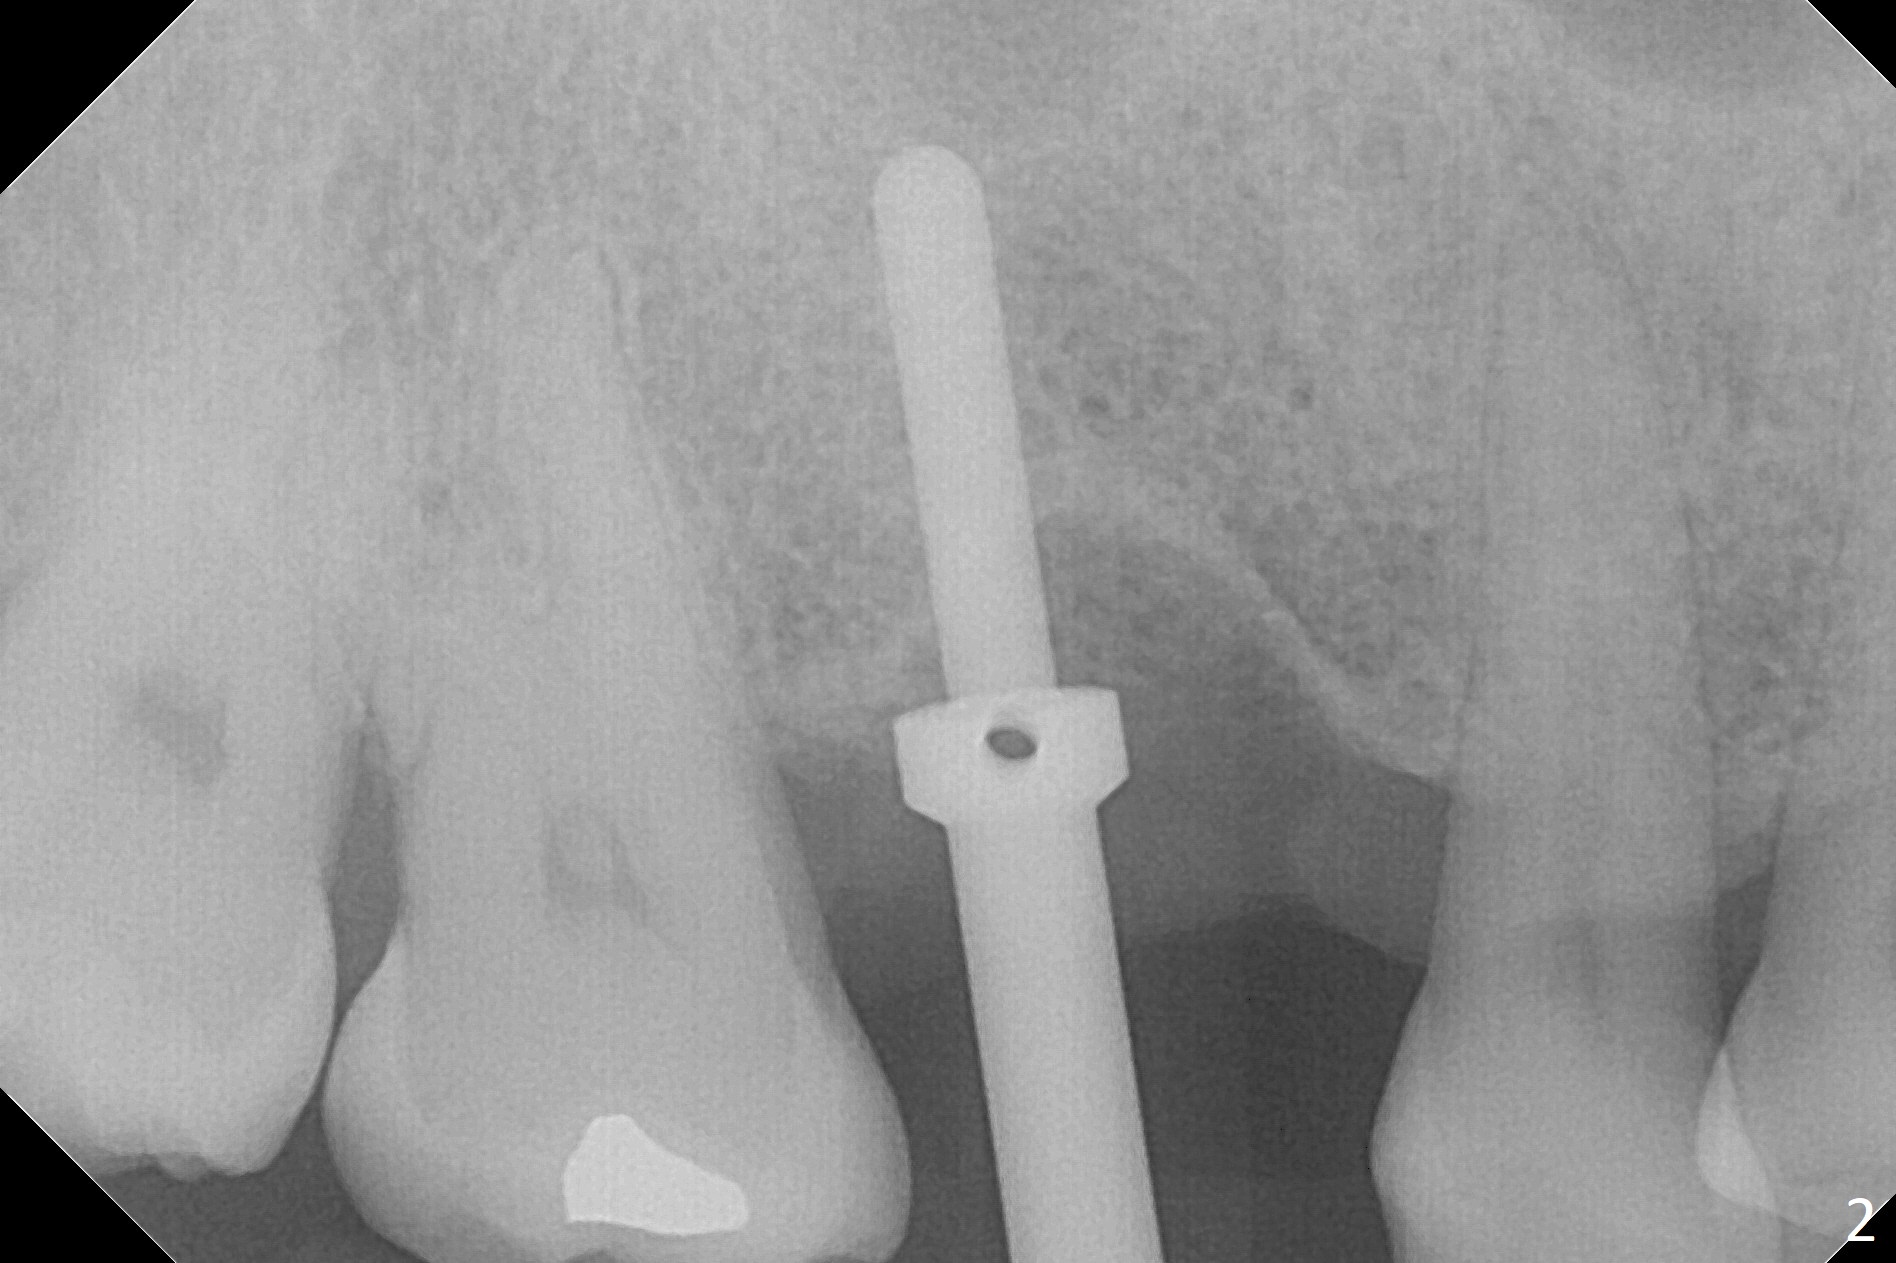

The clearance between the residual roots of the tooth #3 and the abutment at #30 seems to be somewhat limited (Fig.1). The initial osteotomy depth is 10 mm (Fig.2). After moving the osteotomy mesially, the depth increases to 12 mm; a parallel pin is inserted for 16 mm (Fig.3 with sinus membrane perforation). The depth of the rest of the osteotomy is 10 mm with placement of a 5x10 mm implant with >50 Ncm (Fig.4); with insertion of a 6.8x4(3) mm abutment and Vera Graft (*), an immediate provisional is fabricated. Collagen plug is used to seal the gap between the provisional and the gingiva. The abutment dislodges nearly 1 month postop; the wound has healed (Fig.5). A 8.2x5(4) mm healing abutment is placed to keep the soft tissue configurement.